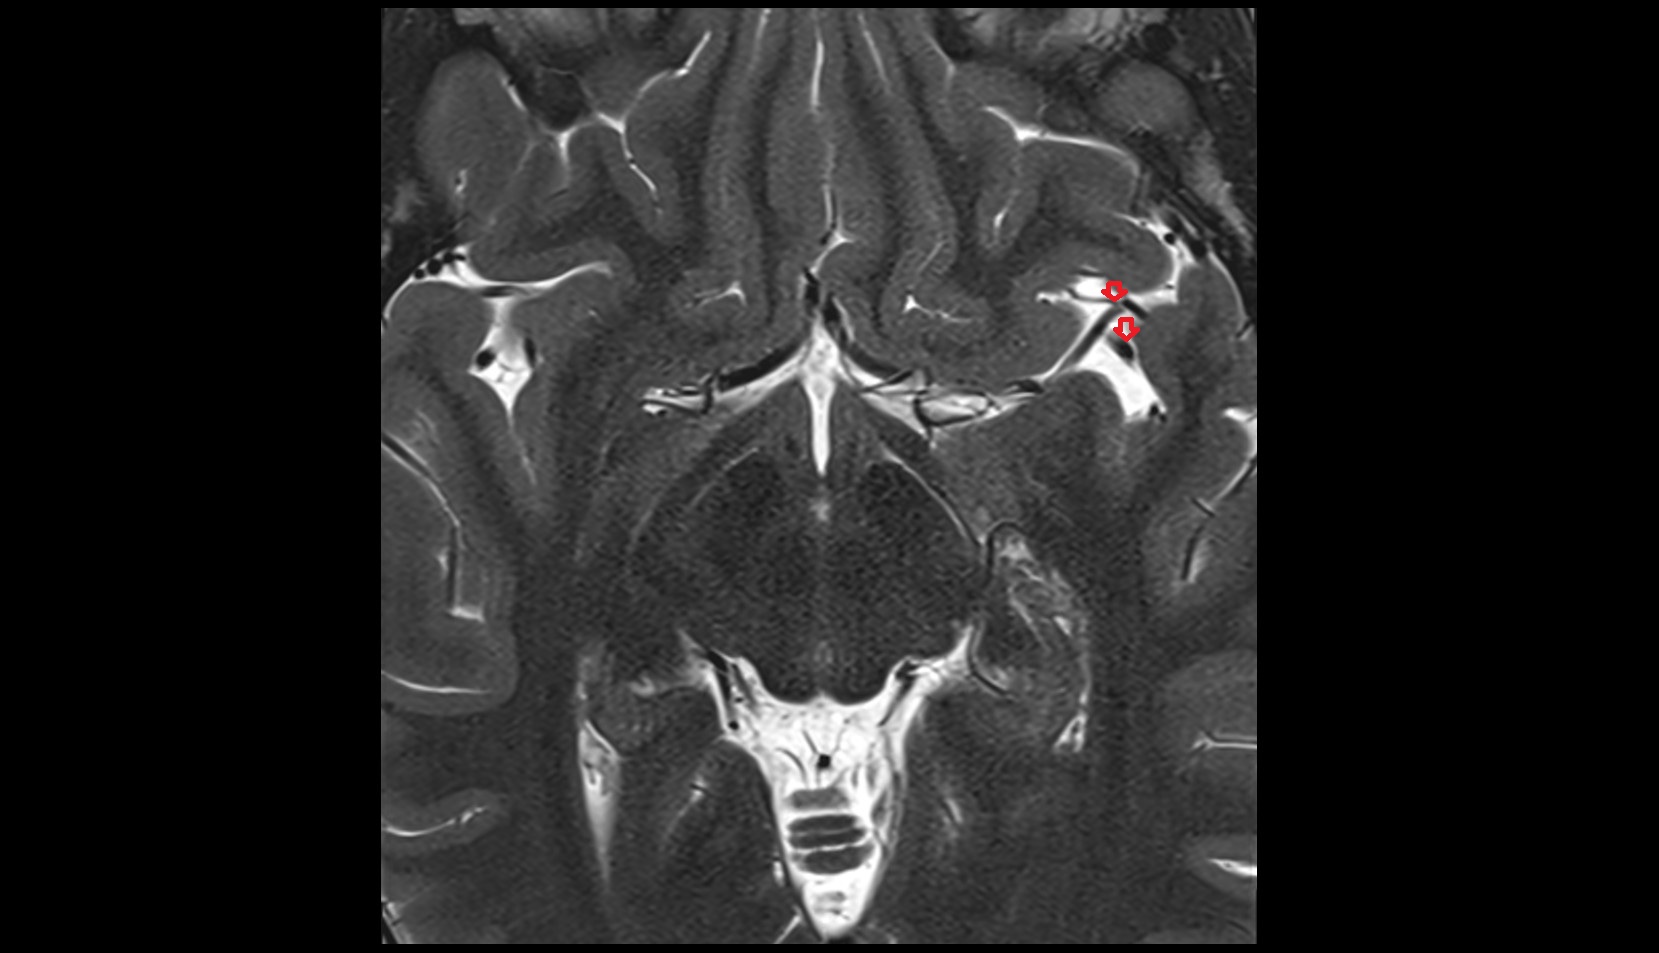

- Lateral aperture of fourth ventricle (foramen of Luschka)